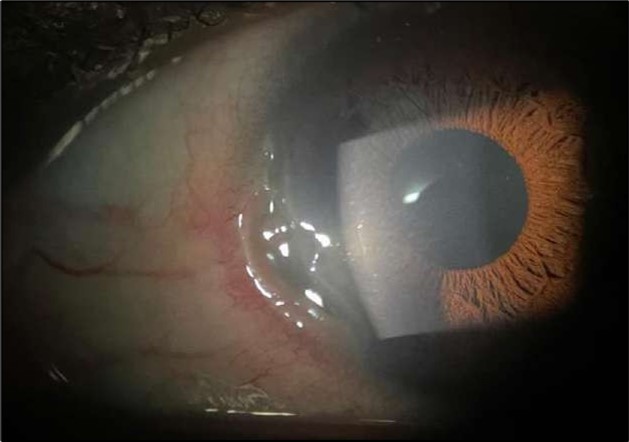

Despite systemic and topical management over one month, the epithelial defect persisted, indicating refractoriness to medical therapy. OCT imaging showed ulcer depth reduction to nearly 42% stromal thinning and width of 1180 µm, highlighting partial corneal healing. In view of the persistent ulcer and ongoing local inflammation, a conjunctival resection was performed to excise the perilimbal inflammatory focus and promote corneal repair Figure 3a and 3b.

Figure 3a and 3b.OS, Intraoperative photo showing excision of a 4 mm-wide strip of perilimbal conjunctiva between 7 and 10 o’clock, adjacent to the area of stromal ulceration.